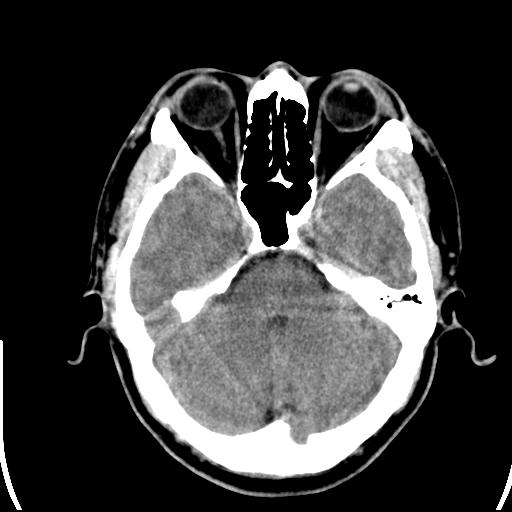

头皮下高密度结节影???临床上在老年男性比较常见。大家看看是什么?成因是? 本例患者,男性,51岁。外伤来诊。无染发史及发根植入史。

考虑异物。

皮下钙化点

没见过,可能为毛囊钙化。

考虑钙化。